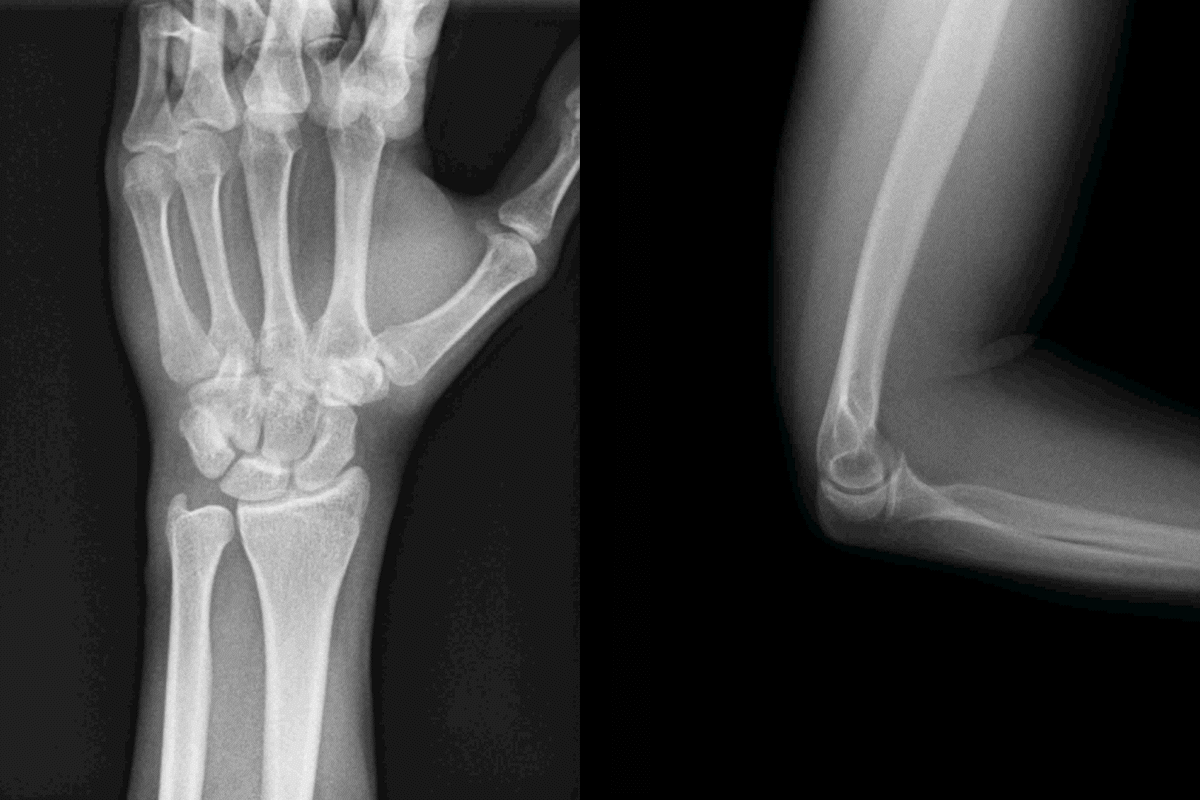

Una de las principales ventajas de esta tecnología se encuentra en los estudios ortopédicos, puesto que permite observar el movimiento de las articulaciones, como la muñeca, el hombro o la rodilla. Este resultado es especialmente útil para evaluar posibles lesiones o disfunciones en estas áreas, con una investigación más precisa y personalizada en el tratamiento de los pacientes.